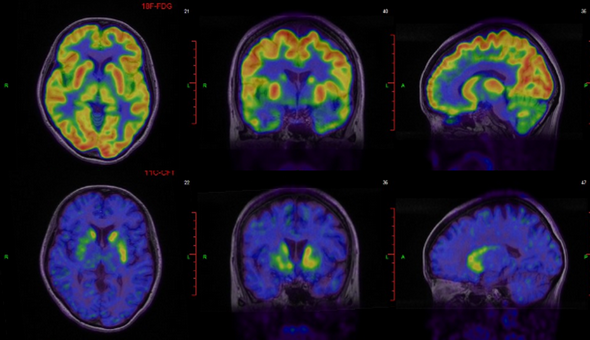

帕金森綜合征(PD)患者行18F-FDG和11C-CFT顯像,18F-FDG顯像提示腦左右半球沒有差異,但11C-CFT顯像可以看出明顯差異,聯合18F-FDG和11C-CFT顯像,可以輔助PD的診斷和鑒別診斷(如下圖)。